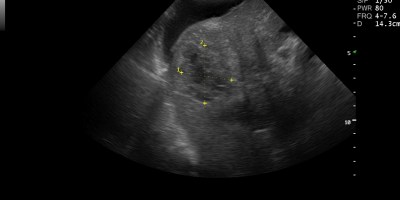

Abdominal Ultrasound, Υπέρηχος κοιλίας Hepatocellular Carcinoma/ ΗΠΑΤΟΚΥΤΤΑΡΙΚΟ ΚΑΡΚΙΝΩΜΑ 26 Δεκεμβρίου, 2012